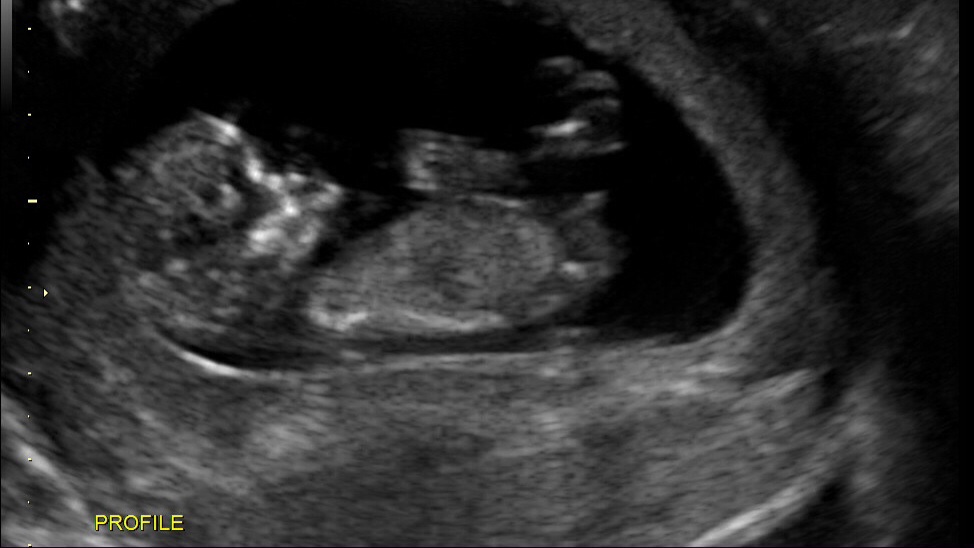

I have my anatomy scan next week so I'm just curious to see what you all think based on these two theories. So, what's your thought boy or girl? Thanks.Attachment 15671Attachment 15672

Very clear boy nub

looks boy to me too

boy

That's definitely a boy.